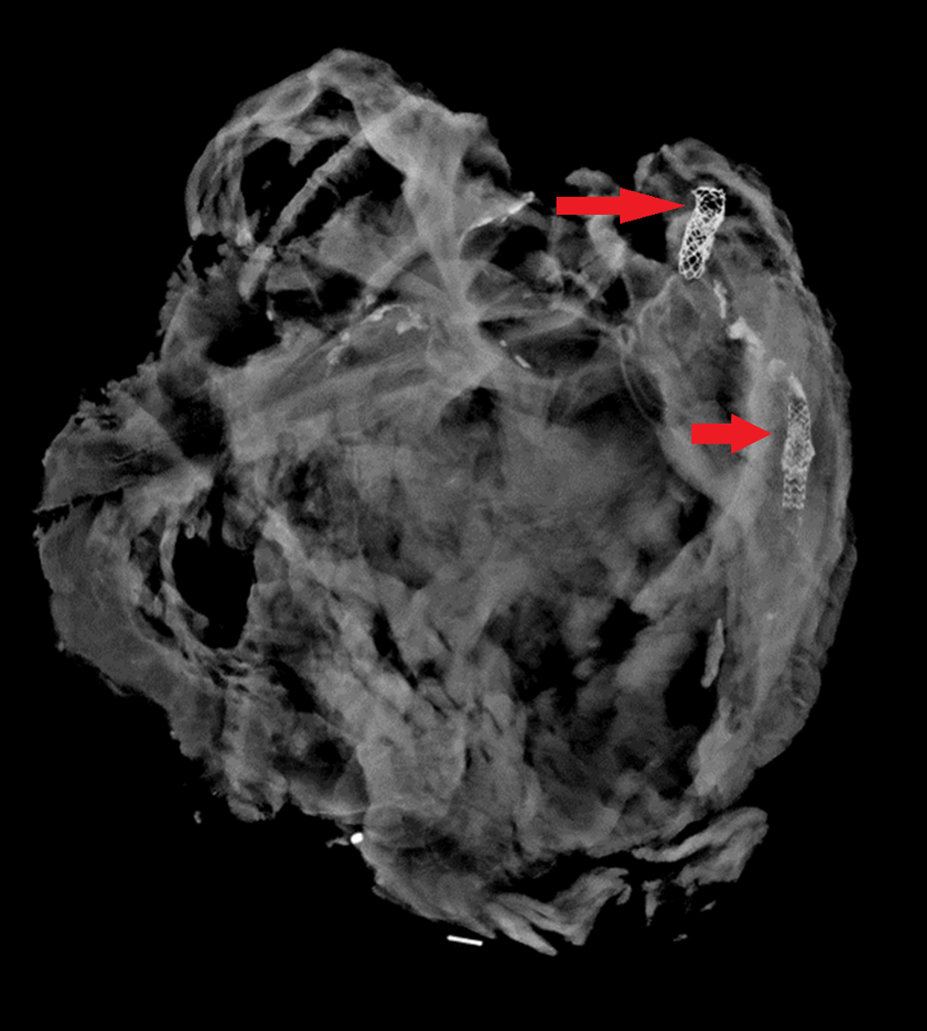

The second pathway by which we reach an undetermined manner is when extensive decomposition or other soft tissue loss (such as fire damage) interferes with our ability to determine a cause of death. Think of completely skeletal remains discovered in an abandoned building. Sometimes, indicators of potentially lethal injuries can still be identified – for example, a gunshot wound of the skull or knife marks on a rib. But, as the aphorism goes, “an absence of evidence isn’t necessarily evidence of absence” – a bullet or blade could be lethal while only striking soft tissue (especially in regions like the abdomen or neck). If we cannot rule out non-natural causes of death, the best choice for manner is “undetermined.”